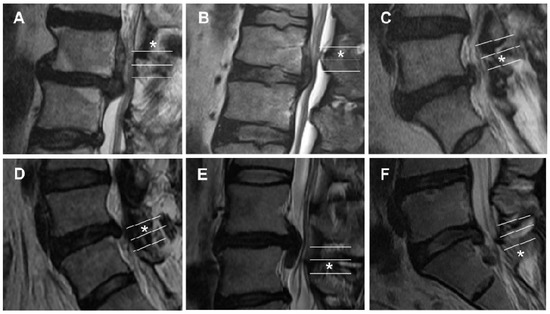

| Grade | Direction and Degree | Range of Migration Distance |

|---|---|---|

| 1 | Superior very high | Beyond the inferior margin of the upper pedicle |

| 2 | Superior high | From the inferior margin of the upper pedicle to the midpoint between the inferior margin of the upper pedicle and superior disc margin |

| 3 | Superior low | From the midpoint between the inferior margin of the upper pedicle and superior disc margin to the superior disc margin |

| 4 | Inferior low | From the inferior disc margin to the midpoint between the inferior margin of the lower pedicle and inferior disc margin |

| 5 | Inferior high | From the midpoint between the inferior margin of the lower pedicle and inferior disc margin to the inferior margin of the lower pedicle |

| 6 | Inferior very high | Beyond the inferior margin of the lower pedicle |